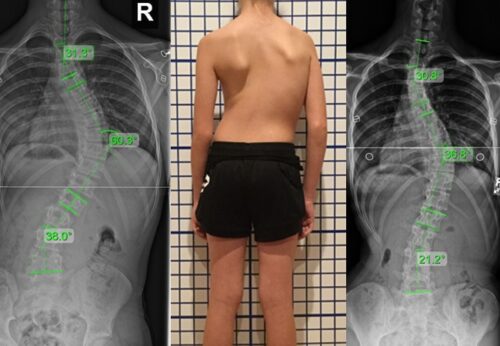

تُظهر الأدلة أن الحزام خيار فعّال وموثوق في علاج اعوجاج العمود الفقري، خاصة في حالات الانحراف القطني والصدري السفلي. كما تُشير النتائج إلى أن الحزام لا يُستخدم فقط لتقويم الانحناء، بل يساهم أيضًا في تحسين التوازن الجسدي والمظهر العام.